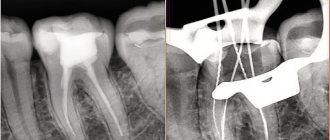

Чтобы точно определить, каково состояние костной ткани пациента, стоматологи обращаются к двум основным методам диагностики:

1. Ортопантомограмме.

2. Компьютерной томографии.

Ортопантомограмма является обширным снимком, позволяющим изучать состояние челюсти при подготовке к имплантации. Благодаря такой процедуре врач получает важные данные относительно зубных корней, расположенных недалеко от гайморовых пазух, объема костных структур, и разрабатывает последующий план лечения.

Компьютерная томография, основанная на лучевой диагностике, позволяет получать послойные снимки костной ткани, помогающие детально изучить ее состояние в участке запланированной имплантации. Отличием КТ от других диагностических методов является возможность иметь не плоское, а 3-мерное изображение, максимально точно определять качество костной структуры челюсти, ее ширину и толщину.

КТ сравнительно нашла свое применение в стоматологии (на протяжении нескольких последних лет). Важными преимуществами данной диагностической процедуры являются высокая четкость изображения, отсутствие искажений, способность точно определять размеры недостаточно видимых глазу объектов, быстрота обследования (проведение процедуры ограничивается несколькими минутами), меньшая в сравнении с рентгеном лучевая нагрузка.